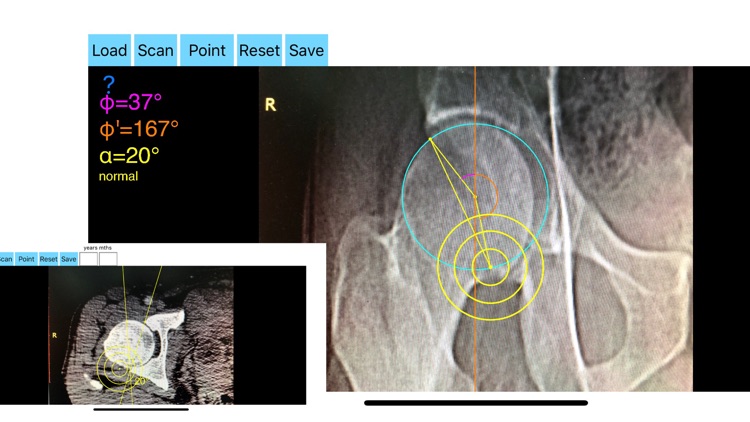

AcetabularAnteversionApp screenshot-0

-By marking certain points in a simple standard AP pelvic radiograph, geometric parameters are being calculated. The App computes the acetabular anteversion based on a pelvic AP radiograph. The angle of anteversion is calculated through the formula according to Heftis nomogram. The acetabular orientation (anteversion/retroversion) is determine by the app by the measurement of the angles between the center of the femoral head and the anterior (φ) and posterior (φ’) acetabular rim.

Once you choose correctly the anterior and posterior acetabular rims the app calculates the acetabular anteversion based on nomogram.

-The data are printed over to screen so each case can easily assessed